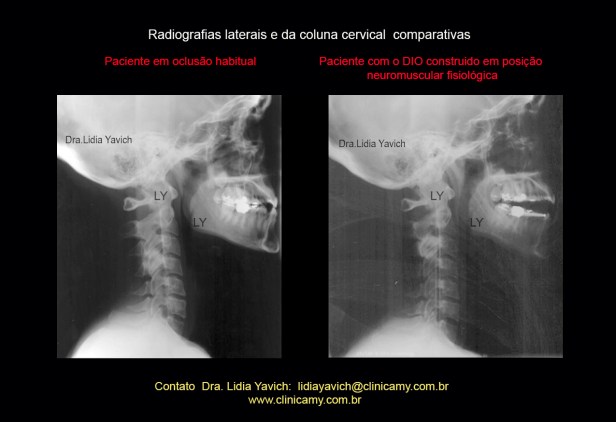

Comparação das radiografias laterais e perfil da paciente: em oclusão habitual antes do tratamento e com o DIO (dispositivo intraoral), em posição neuromuscular fisiológica.

Comparação das radiografias laterais e perfil da paciente: em oclusão habitual antes do tratamento e com o DIO (dispositivo intraoral), em posição neuromuscular fisiológica.

Comparação das radiografias laterais e da coluna cervical da paciente: em oclusão habitual antes do tratamento e com o DIO (dispositivo intraoral), em posição neuromuscular fisiológica.

Comparação das radiografias laterais e da coluna cervical da paciente: em oclusão habitual antes do tratamento e com o DIO (dispositivo intraoral), em posição neuromuscular fisiológica.